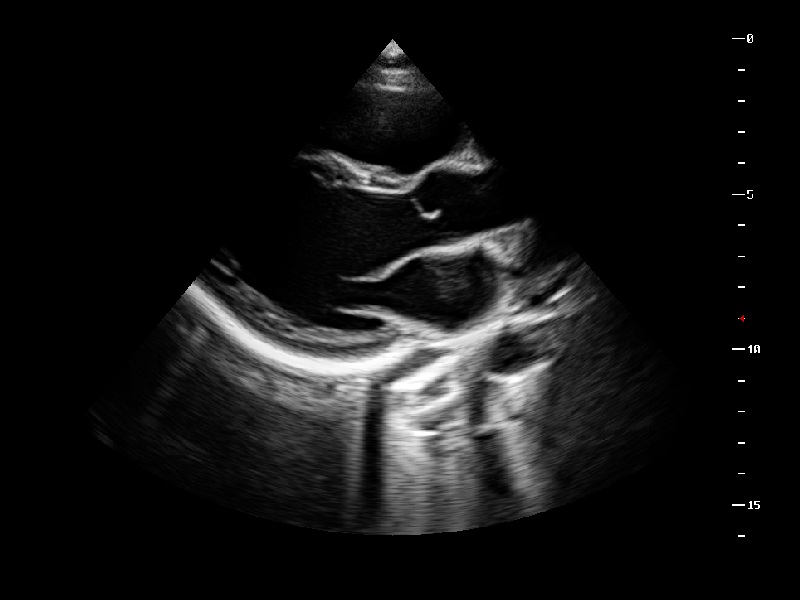

Stress echo is used to diagnose coronary heart disease, evaluate coronary reserve function and myocardial ischemia, and estimate myocardial viability, providing valuable diagnostic information for PCI&CABG.

1Mhz Low Frequency Convex transducer greatly improve the Piezoelectric crystal signal ratio, Acquire stunning Quality Images & New Generation μ-Scan + Provide High sensitivity & High Resolution for the Both near and far field, 200 degree Transvaginal Probe provides extraordinary image quality for gynaecology, Early Obstetrics scan, HD Linear Transducer achieve a Uniform image Quality, high sensitive acoustic spectrum in vascular, brest, MSK, Thyriod, Lower and upper limp, Etc and Aeroscan CD40 enhancing boundary improved visualization in 2D and Color Doppler in Echocardiogram with all premium Features loaded., CD40 Supports Ultras-wide Frequency bandwith Probes - Intra-operative, Paediatric, Neonatal, TEE, Transrectal, Volume Transducer & More.,